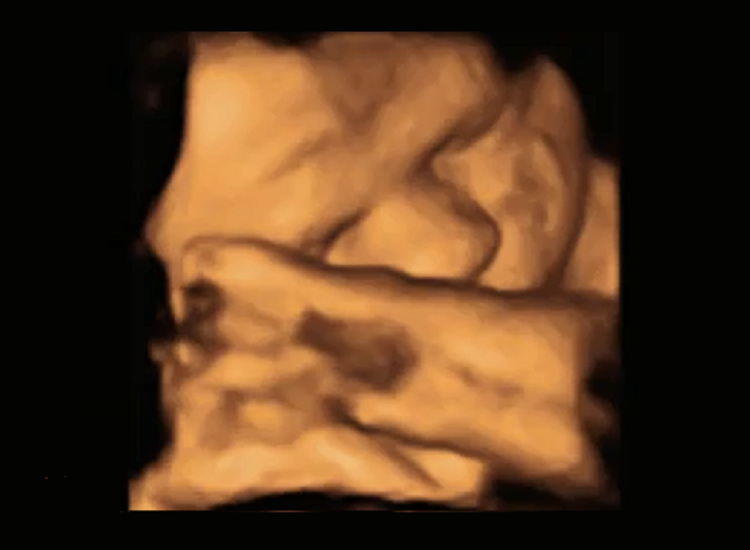

The visual development of babies in the womb has been explored for the first time ever, revealing a clear preference for face-like shapes. Researchers have found that fetuses at 34 weeks are like…